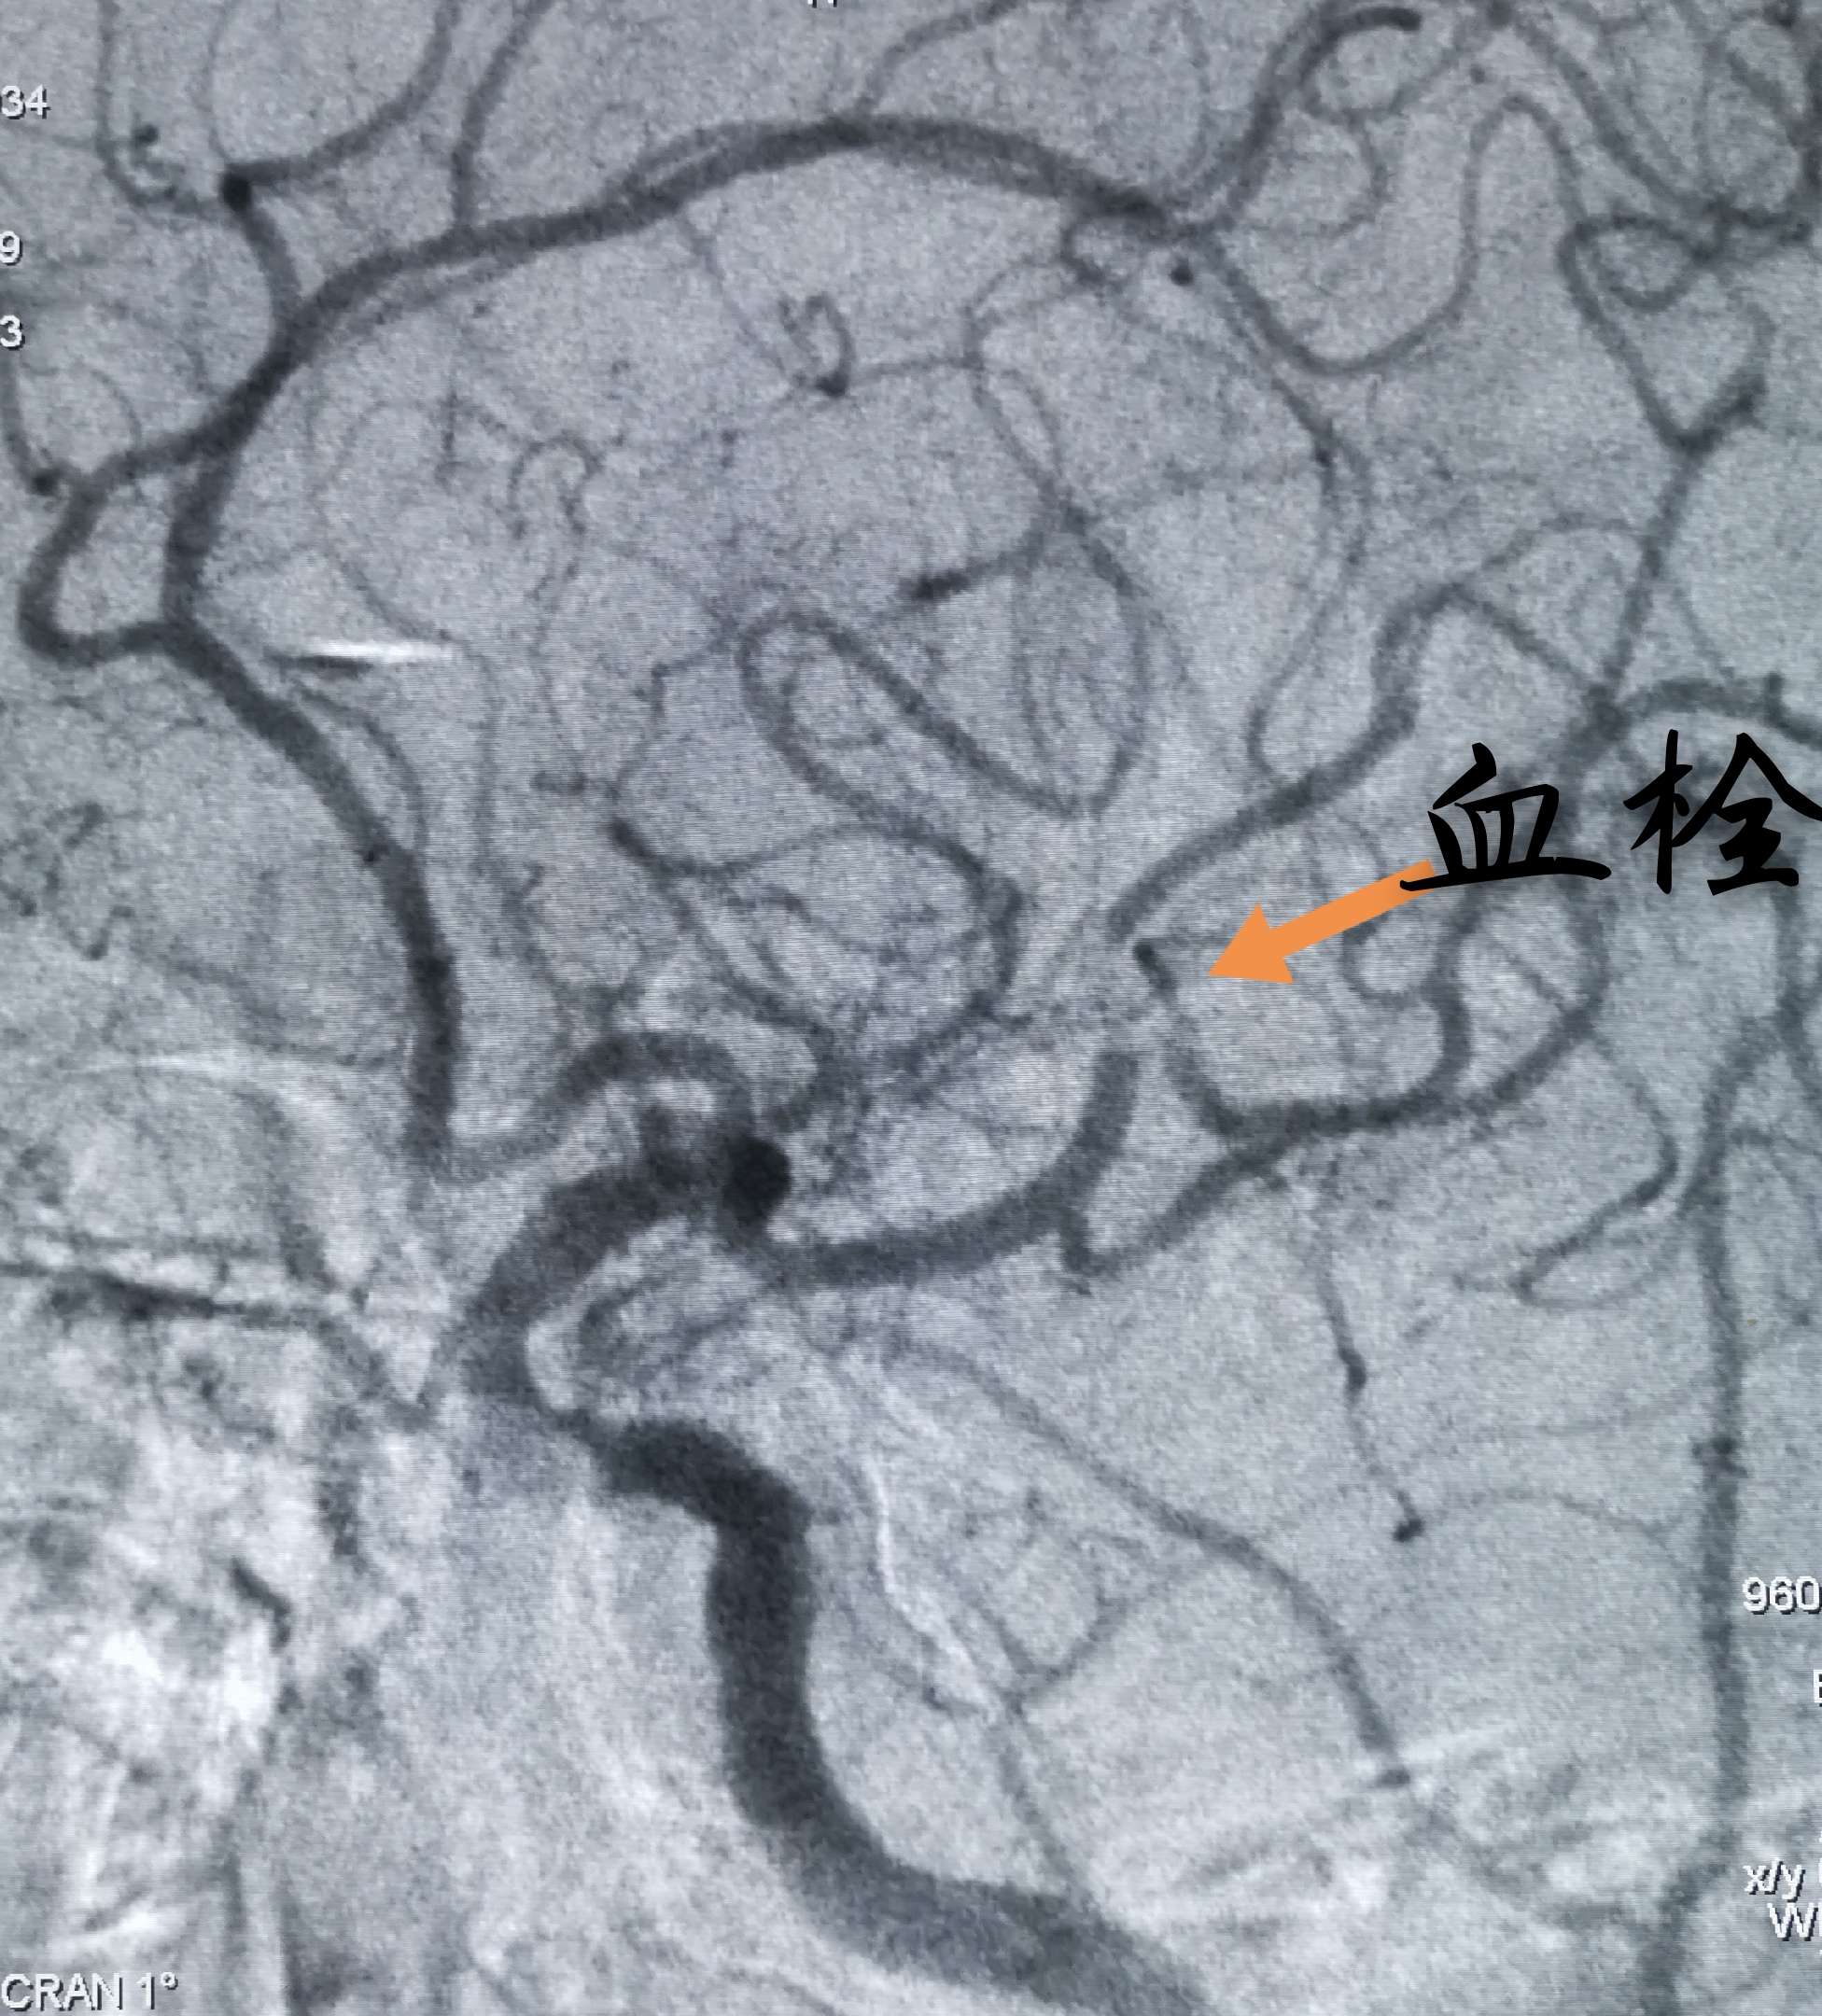

快速转运并完成DSA,发现右侧大脑中动脉M2、M3分叉处血栓,两大分支血流缓慢

Guiding内造影发现M3分支不显影